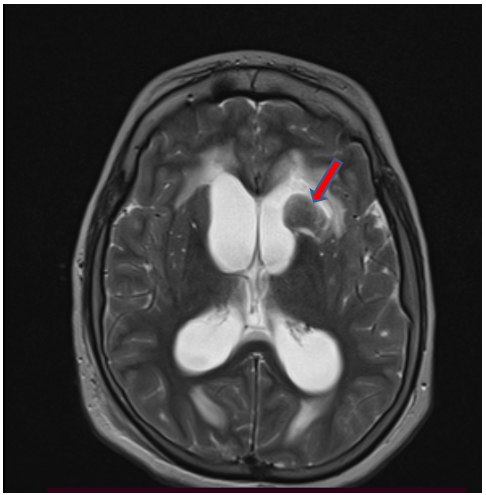

Case Report

A Pediatric Case: Supratentorial Cerebral Tuberculoma

Sanae Jellal, Rachida Chehrastane, Jihane El Houssni, Sara Zenjali, Lina Belkouchi, Siham El Haddad, Latifa Chat and Nazik Allali. 13(7): 01-03.